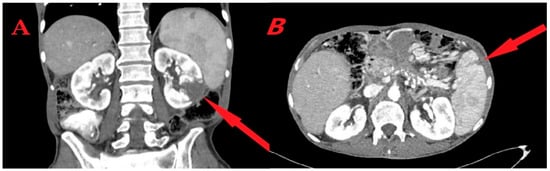

Blood tests demonstrated mild normocytic anemia (12.30 g/dL), normal leukocyte count (8610/mm3) with 80% neutrophils, and mild thrombocytopenia (132,000/mm3). C-reactive protein was elevated (103 mg/L—normal value < 6 mg/L), liver enzymes were mildly elevated, bilirubin, amylase, lipase, and renal function tests were within normal ranges, and urinalysis was normal. An abdominal computerized tomography (CT) scan with intravenous contrast revealed a wedge-shaped parenchymal defect in the inferior aspect of the left kidney (Figure 1A), and a smaller wedge-shaped parenchymal defect in the spleen (Figure 1B). These two findings were highly suspicious for infarcts. Five out of six blood culture sets obtained on admission were positive for ampicillin-sensitive Enterococcus faecalis.

Figure 1.

Abdominal CT scan. (A) Left kidney infarct—a wedge-shaped parenchymal defect in the inferior aspect of the left kidney (arrow). (B) Splenic infarct—a wedge-shaped parenchymal defect in the spleen (arrow).